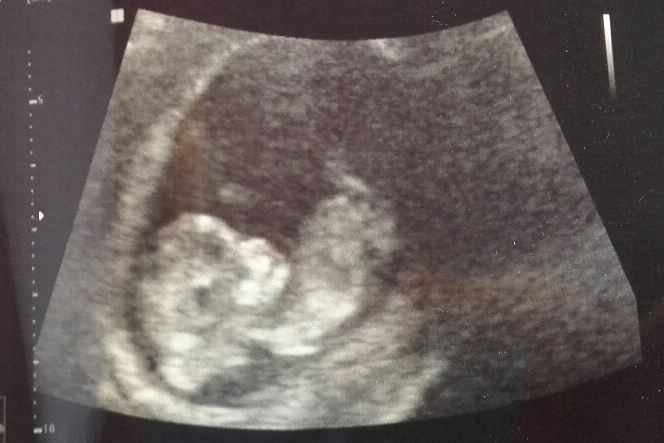

Si hei til lille Ræga :strix:

Her var det liv som bare det :danse: Hjerte slo og lille lå og slappet av med den ene hånda si bak hodet :rodmer:

Tenk at det faktisk er et lite menneske INNI meg. Herregud det er helt utrolig at det går an :bond:

Det var såååå deilig å få se det. Føler meg et tonn lettere :bolledeig:

Ja det er helt utrolig. H*n lå inni der med ene armen under hodet og slappet av. Lå opp ned og kosa seg. Gyn dulta i magen min for å se om ho fikk noe respons. H*n bare snudde ryggen til :fnise:

Merker at jeg nå ble litt mer nysgjerrig på om det er gutt eller jente :lur: Mest fordi jeg har jentefølelse, mannen synes det ligna på ei jente på bildet (lol) og gyn kalte h*n for HAN :P Men ho sa at ho kaller alle for han :fnise: